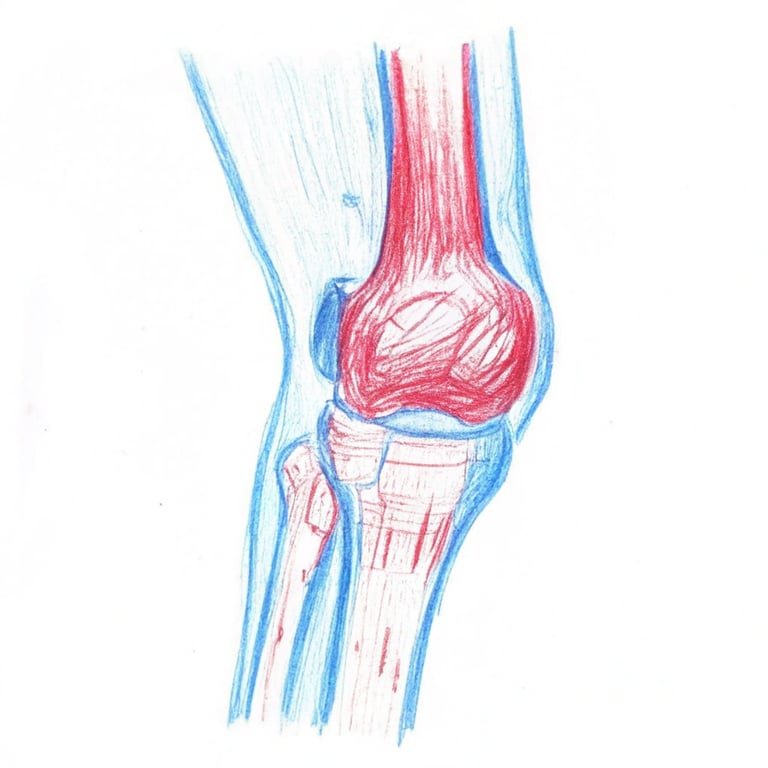

我們的膝關節是人體最大的承重關節,由大腿骨(股骨)、小腿骨(脛骨)和膝蓋骨(髕骨)組成。這些骨頭的接觸面都覆蓋著一層平滑且富有彈性的關節軟骨。這層軟骨就像一個避震墊,不僅能減少骨頭之間的摩擦,讓關節活動順暢,還能吸收走路、跳躍時產生的衝擊力。然而,隨著年齡增長,關節軟骨會逐漸的失去水分和彈性,慢慢磨損以及變薄、變粗糙。

示意圖

當軟骨磨損嚴重時,骨頭與骨頭之間缺乏軟骨保護,直接摩擦,就會引起關節發炎、疼痛。為了穩定關節,骨骼邊緣還可能增生出骨刺,導致關節空間變窄,活動更加受限。